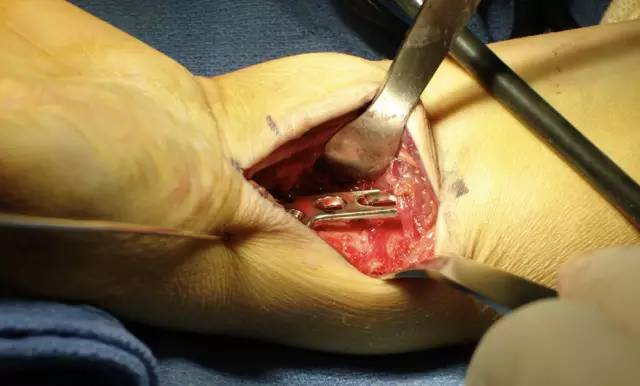

在桡腕关节中插入一枚克氏针,这有助于确定桡骨最远端的界限。如果存在关节边缘的小骨折块,可将掌侧 2.4 mm 钢板放置在桡骨远端关节边缘进行固定。换句话说,月骨关节面的小骨折块可用 2.4 mm「L」或「T」型钢板进行支撑,如图 2。

图 2. 复杂的掌侧关节内骨折,应用两块「L」型钢板进行支撑

4. 在置入钢板之前,用牵开器撑开,充分显露术野:

5. 在远折端靠近软骨下骨置入远排锁定螺钉: